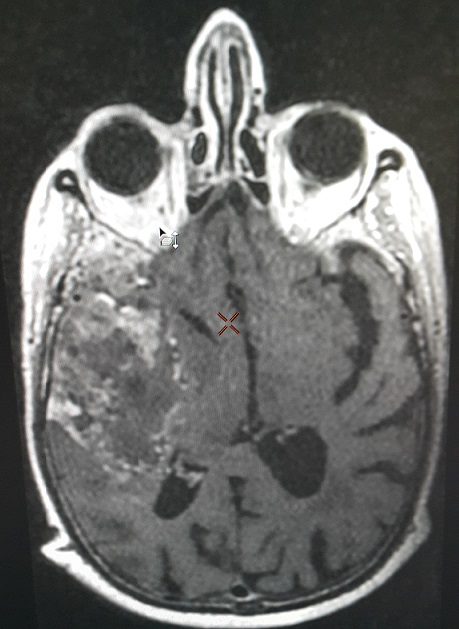

Brain metastasis from male breast cancer treated 12 years ago

Male breast cancer is an uncommon disease that has been the focus of limited researches. Its etiology is unclear, but hormonal levels may play a role in the development of this disease. Our case is a 84 year old patient treated for breast cancer 12 years ago, it was an infiltrating ductal carcinoma classified pT2 N0 M0 with hormone receptor positive (HR +), treated with surgery, adjuvant chemotherapy, radiation therapy and 5 years of endocrinotherapy (tamoxifen 20mg 1 tablet daily continuously). Clinical control of our patient was normal within 11 years and 10 months. A month ago, the patient had headache and vomiting complicated by the sudden onset of left hemiplegia. The brain MRI showed a huge right temporal process with a shift of the midline structures (figure). A biopsy was also performed and demonstrated a cerebral relapsed breast primitive with the same disease profile (HR positive and HER2 negative). Brain metastases traditionally occur in 10-16% of metastatic breast cancer patients and are associated with a bad prognosis. The development of brain metastases has been associated with young age, and tumors that are estrogen receptor negative, HER2 positive or of the basal phenotype. However, we can also have brain metastases of a primary breast cancer in elderly patients even with pathological and immunohistochemistry different profiles regardless of gender.